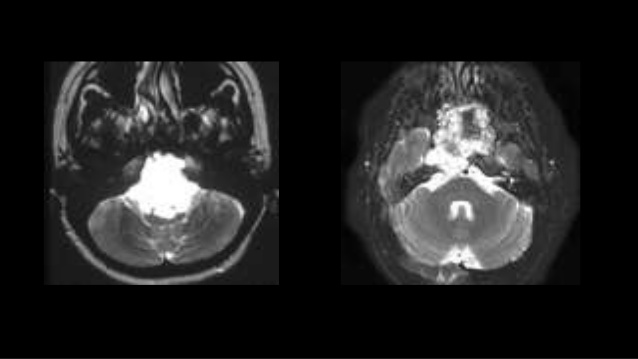

脊索瘤是一種起源于胚胎脊索殘余的局部侵襲性腫瘤。使用監(jiān)測、流行病學(xué)和較終結(jié)果數(shù)據(jù)庫的基于人群的研究表明,每106人脊索瘤發(fā)病率為8.4。盡管斜坡脊索瘤占全部脊索瘤的三分之一,但它們僅占顱底惡性腫瘤的0.1%,這使得他們的臨床研究困難。局部復(fù)發(fā)是這些患者死亡較重要的評估因素;因此,無論輔助放療或不輔助放療全切除(TR)被認(rèn)為是治療的主要方法。斜坡脊索瘤的手術(shù)是具有挑戰(zhàn)性的,因?yàn)橄蛑車窠?jīng)血管結(jié)構(gòu)的浸潤是常見的,而且生活質(zhì)量的惡化可能是相當(dāng)嚴(yán)重的。脊索瘤能活多久?中位生存期為7.7年。

脊索瘤的特征在于進(jìn)行性局部生長,并具有局部復(fù)發(fā)的趨勢。顱底脊索瘤的普遍接受的治療方法是切除,然后進(jìn)行輔助放射治療,以根除殘留的疾病。手術(shù)的全切除是影響預(yù)后的主要因素。

內(nèi)鏡技術(shù)的前沿進(jìn)展現(xiàn)在可以好轉(zhuǎn)進(jìn)入顱骨中部的通道,并降低了與鼻內(nèi)手術(shù)相關(guān)的并發(fā)癥的發(fā)生率。與部分切除的患者相比,全切除患者的結(jié)果更好。在部分切除的患者中,輔助治療可好轉(zhuǎn)預(yù)后。例如,與僅接受TR的患者相比,未經(jīng)輔助治療的部分切除患者的復(fù)發(fā)率高2.6倍。手術(shù)和輔助放療后的5年無進(jìn)展生存期PFS(65.7%)。